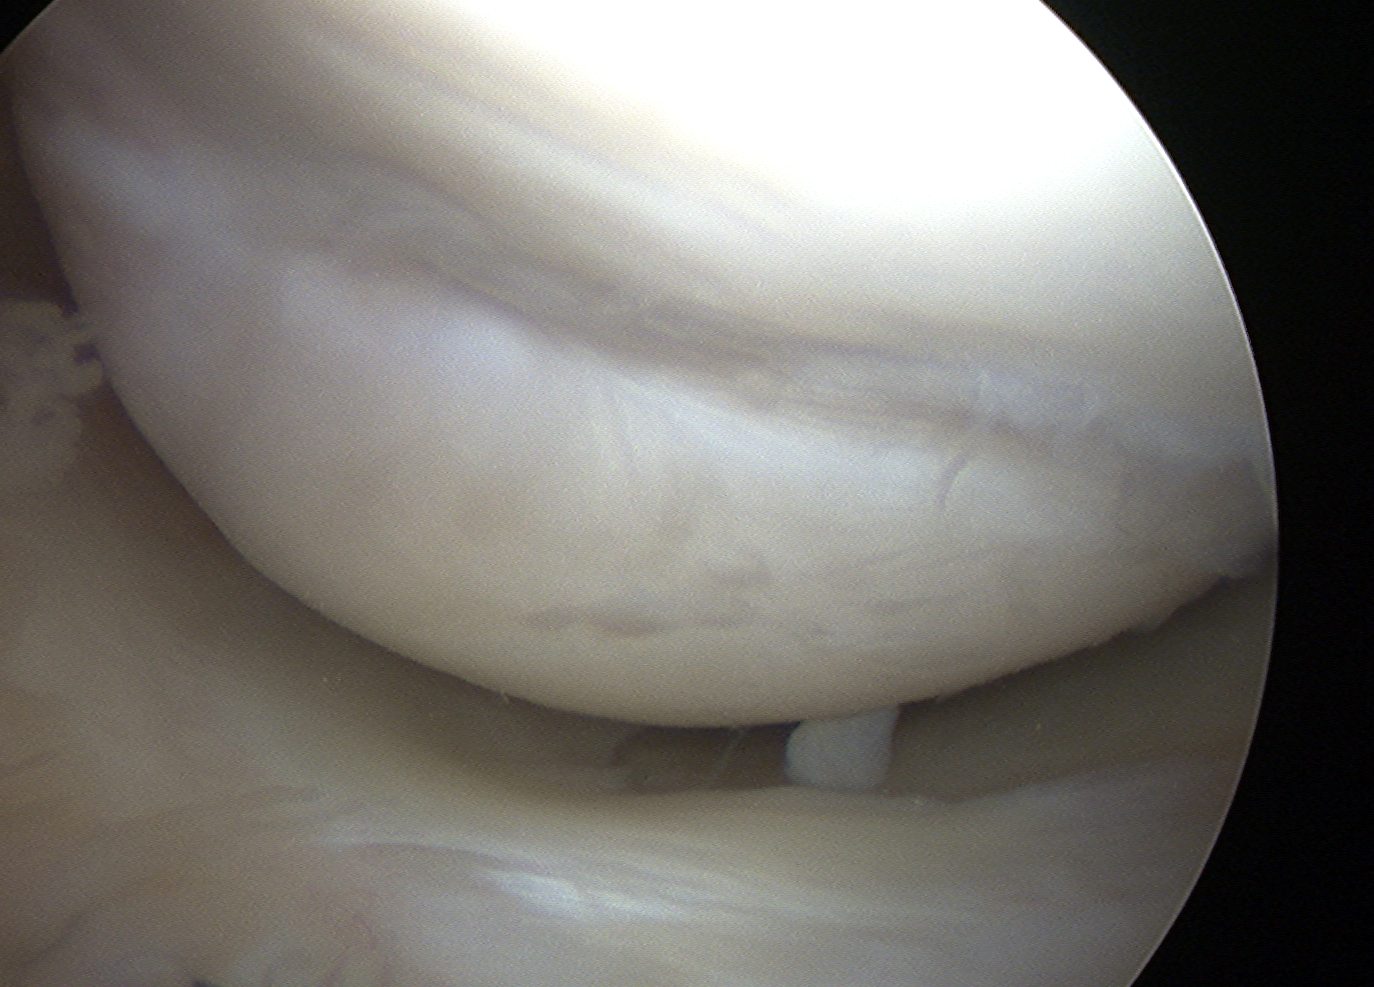

Arthroscopy images of right knee demonstrating normal ACL

Normal ACL on MRI

Characteristics

- straight structure

- able to see continuity of fibres from tibial to femur

- parallel to intercondylar notch

- no anterior subluxation of the tibia

- normal to have some increased signal due to adipose and synovial tissue